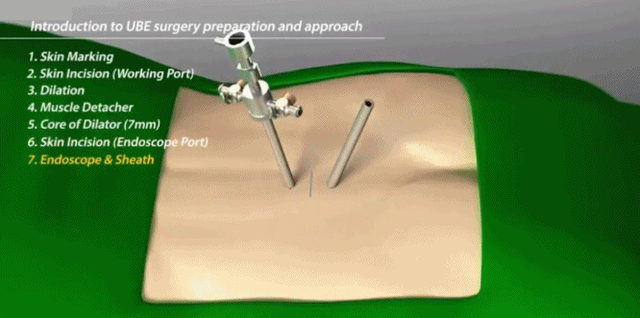

UBE技术即单侧双通道内镜技术(Unilateral Biportal Endoscopy Technique),适用于颈椎、胸椎、腰椎的退行性病变。与椎间孔镜的单通道不同,该技术通常建立两个通道,一个为观察通道,一个为器械操作通道。在UBE内镜辅助下可完成中央椎管、双侧神经根及侧隐窝狭窄的减压,并可在镜下进行椎间植骨融合的一项技术。

UBE的技术特点:

1.兼有内镜放大的视野和开放手术灵活的操作;

2.应用常规椎间孔镜器械和脊柱开放手术器械;

3.对肌肉损伤较小、透视少;

4.可以镜下融合;

5.对椎管狭窄具有独特的优势;

6.有内镜操作经验者学习曲线较短;

7.条件成熟同样可以用于颈胸段。